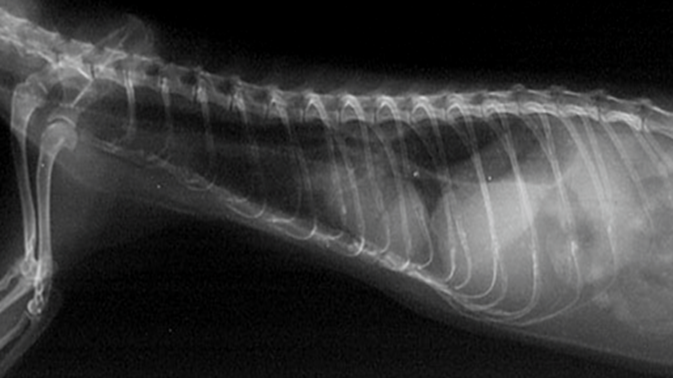

X線検査で食道が拡大(拡張)し、正常な運動性が欠如している状態を指しますが。

鑑別診断には食道または胃腸の異物、胃炎、および呼吸器疾患が含まれます。X線検査では食道が拡張あるいはガスが貯留しており、確定診断のために硫酸バリウムまたはイオヘキソール(経口投与 [PO] で 8~10 mL/kg)を投与します。フェレットは注射器で強制的にバリウムを摂取しますが、食道破裂の可能性がある場合には、バリウムの代わりにイオヘキソールを使用します。造影剤が食道の輪郭を描出し、巨大化していることで診断されます。